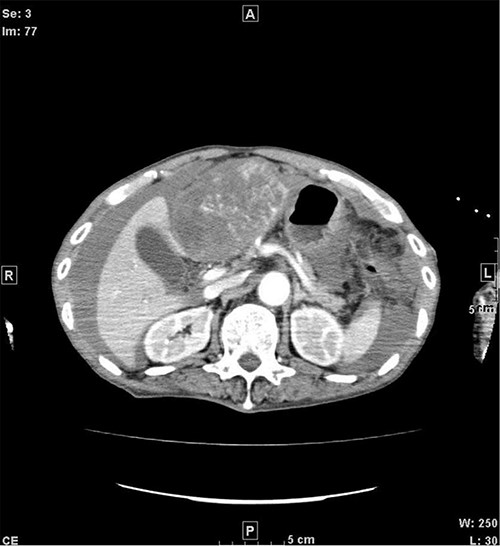

A 77-year-old man was referred to the Department of Gastroenterology at our hospital for suspicion of hepatocellular carcinoma and cancerous peritonitis. He was scheduled to be hospitalized for a thorough examination at a later date. However, 3 days after his first visit, he returned to the Emergency Department with a complaint of abdominal distension. He was hospitalized on the same day with a diagnosis of intra-abdominal bleeding due to a ruptured tumor in the lateral section of the liver. Computed tomography (CT) and magnetic resonance imaging (MRI) revealed a tumor with a maximum diameter of 8 cm in the lateral hepatic region and ascites around the liver and in the pelvic floor. Dynamic CT showed blood vessel-like early staining inside the tumor, and the contrast effect gradually enhanced (Fig. 1). During gadolinium ethoxybenzyl diethylenetriamine pentaacetic acid-enhanced MRI, this contrast effect gradually increased from the peripheral part toward the hepatocyte phase from the arterial phase (Fig. 2). Levels of tumor markers (alpha-fetoprotein, protein induced by vitamin K absence or antagonist-II, carcinoembryonic antigen and carbohydrate antigen 19–9) were within the normal range (Table 1). Based on the imaging findings, a diagnosis of spontaneously ruptured hepatic hemangioma was made. Since the patient’s general condition was stable and there were no findings suggestive of active bleeding, he decided to undergo elective surgery. Thus, he was not requested to continue being hospitalized and was discharged. Six days after discharge, he was transported to the emergency room in a state of shock and was hospitalized the same day. With the diagnosis of hemorrhagic shock due to re-rupture of the liver tumor (Fig. 3), emergency transarterial embolization (TAE) was performed. No apparent extravasation was observed on angiography, and A3 was embolized. Seven days later, he underwent left lateral hepatic segmentectomy. The postoperative course was generally good. The post-ruptured tumor was found in the left lateral segment, the cut surface was white, the edges were brown and the boundaries were unclear (Fig. 4). Histopathological examination revealed that sections of the white and brown parts of the margin were viable tumors, showing highly atypical spindle-shaped cells, arranged like sinusoidal vessels and partly solid, and there were many mitotic figures. There was no capsule, and the tumor infiltrated the surrounding liver parenchyma (Fig. 5a–c). Immunostaining showed CD31 (+), CD34 (partially positive), CK-CAM5.2 (−), α-SMA (−), HMB45 (indeterminate) and p53 (+), and the patient was diagnosed with hepatic angiosarcoma (Fig. 5d). Fever was observed 21 days after surgery, and CT was performed, revealing multiple masses in the liver (Fig. 6a). Another CT scan was performed 27 days postoperatively, which suggested that the liver masses were rapidly increasing; hepatic angiosarcoma recurrence was then confirmed (Fig. 6b). The patient requested the best supportive care at home and was discharged 31 days after the operation. He died at home 36 days after surgery.

CT when the patient was transported in a state of shock shows increased bloody ascites but no apparent extravasation. CT, computed tomography.